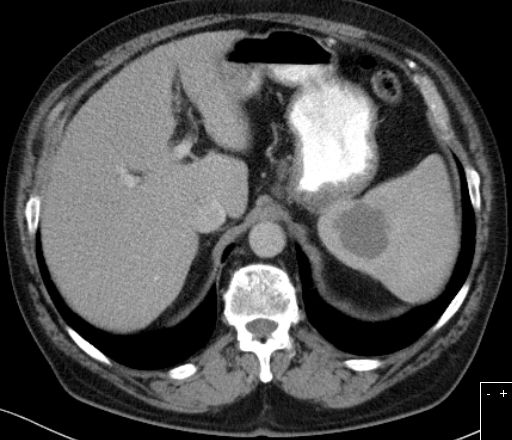

primärer Milzbefall